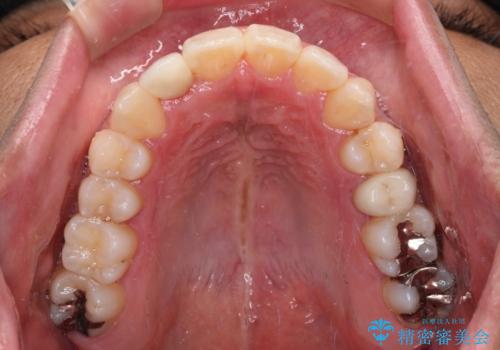

- 前歯のデコボコとクロスバイトを気にして来院された患者様です。

下顎の歯列弓に対して上顎歯列弓がやや小さく、側方の歯を中心にクロスバイトが見受けられました。

後方に隠れていた上顎前歯は矮小歯であるため、矯正治療の途中でオールセラミッククラウンを装着し、左右対称の大きさでの仕上がりを目指すこととしました。

奥歯の咬み合わせは接触が少なく物足りないように見えますが、患者様としては十分に咬むことができるとのことでした。